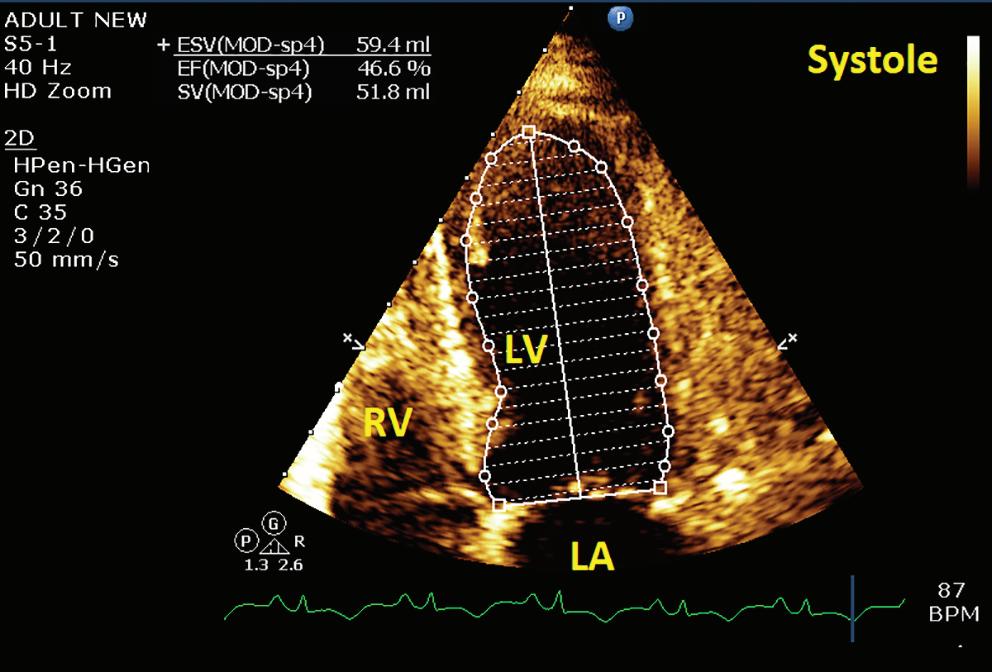

A 57-year-old man presented with a three-decade history of recurrent episodes of palpitation with alarming jugular venous pulsation, but without syncope. Each episode spontaneously reverted to the normal sinus rhythm 6–8 hours after the onset. Cardiac auscultation raised the suspicion of underlying rheumatic mitral stenosis. A 12-lead ECG was suggestive of a WPW pattern with a right posterior septal accessory pathway (Figure 1A). A chest X-ray in the posterior–anterior view was consistent with cardiac auscultation (Figure 1B). A transoesophageal echocardiogram confirmed rheumatic mitral stenosis (Figure 2A and Supplementary Material Video 1). The pliable mitral valve area was 0.8 cm2 and the mean gradient was 17 mmHg at a heart rate of 87 BPM. The coronary angiogram was normal.

On the day of the procedure, the first balloon mitral valvotomy was performed from a right femoral approach using a 23–26 mm Accura balloon (Vascular Concepts) after transeptal access using an 8 Fr SL-1 sheath and a BRK-0 needle (St Jude Medical). A transeptal puncture was performed after proper needle tip position was confirmed by fluoroscopy (right anterior oblique, left anterior oblique and 90° lateral views) and transoesophageal echocardiography (bicaval and short axis views; Figure 3A). The mean left atrial pressure prior to the valvotomy was 31 mmHg. The balloon was inflated to 26 mm in the right anterior oblique 20° position under fluoroscopy (Figure 3B) because the patient was 160 cm tall. The mitral valve area increased to 2.2 cm2 without any additional mitral regurgitation, and the mean left atrial pressure decreased to 12 mmHg without any mitral valve gradient. Immediate transthoracic echocardiography showed that the mitral valve gradient had decreased to 7/2 mmHg with negligible mitral regurgitation.